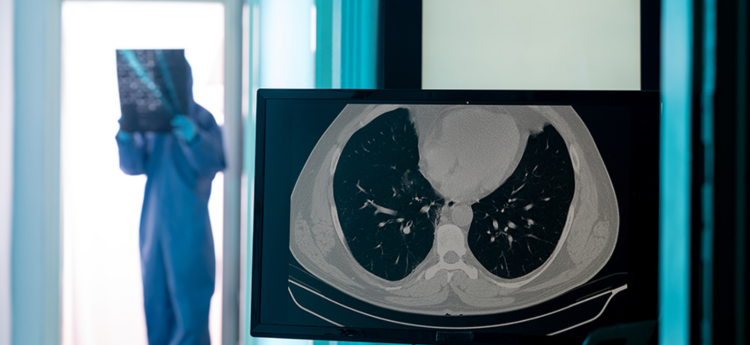

SenseCare®胸部CT肺炎智能分析系统能够一站式自动检测肺炎病灶并提供定性定量分析,同时支持智能精准随访、结构化报告生成等功能,有效辅助肺炎筛查及高效随访。

智能精准筛查

智能识别肺炎病灶,完成高精度分割与勾画

肺炎成分分析

根据病灶分割区域的密度特征自动完成实变影或磨玻璃影分型

精准量化分析

自动进行肺炎感染全肺量化分析,支持根据不同肺炎成分进行量化分析